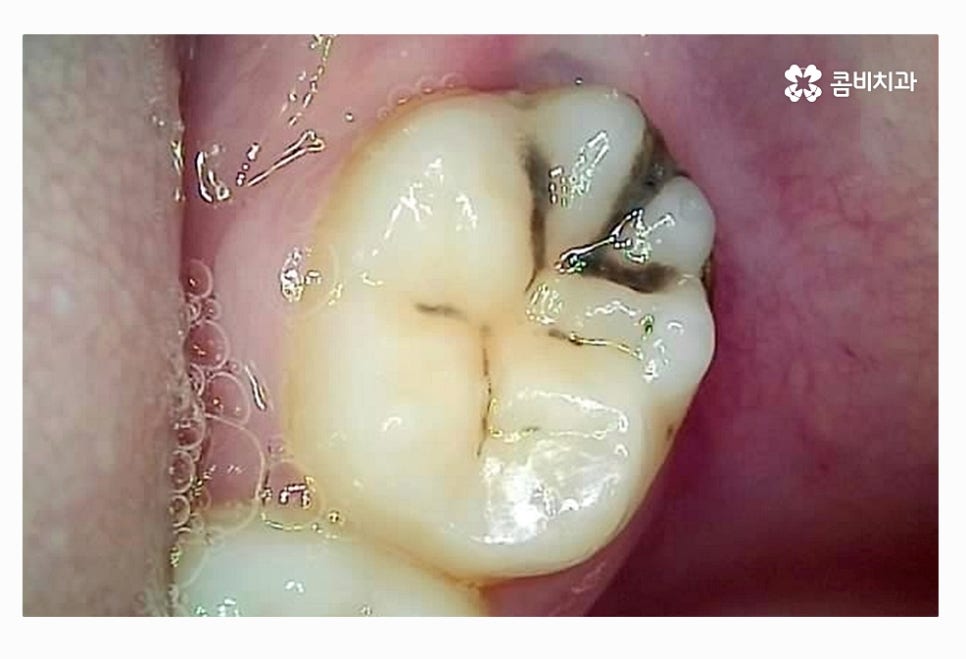

이처럼 사랑니 충치 심해지는 경우에 통증이나

입 냄새 등도 문제겠지만 멀쩡한 어금니 수명을 줄어들게

만들기도 하며 충치 전염, 치주질환 등으로

주변 치아에 안 좋은 영향을 주는 경우도 있는데요.

한국인들은 매복 사랑니로 고생하는 사례도 많지만

정상적으로 사랑니가 맹출 된 경우에도

구강관리가 잘 안되면 사랑니 충치 때문에

결국 발치하게 되는 사례도 많다고 할 수 있어요.

위 환자분처럼 사랑니가 정상적인 위치에서 맹출이 되었다면

청결 관리를 잘한다면 사랑니는 꼭 무조건 발치를

해야 하는 것은 아니지만 사랑니 자체가 치아 중에서도

가장 안쪽에 위치하고 치석 등이 쌓이기 쉽기 때문에

평소 칫솔질을 꼼꼼하게 하더라도 썩기 쉬울 수 있는데요.